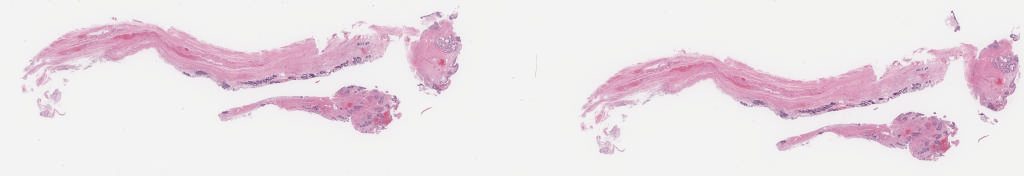

1625958.svs

40X